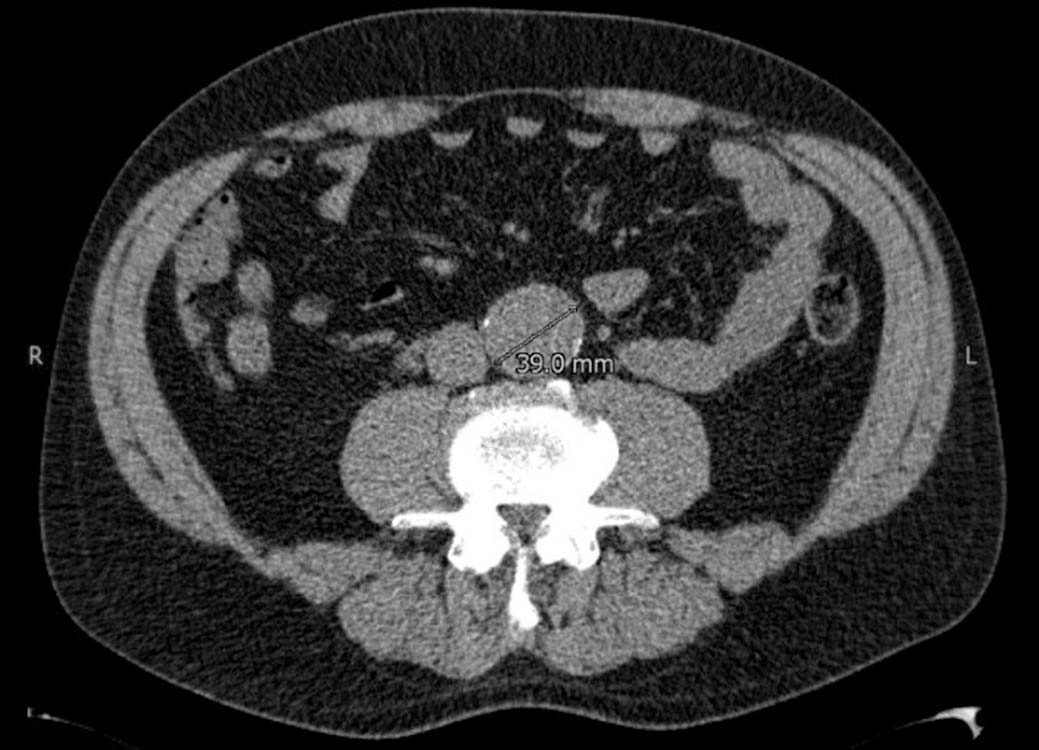

Een snelgroeiend aneurysma van de buikaorta

Soms wordt op een echo of CT van de buik een aneurysma aortae abdominalis (AAA) ontdekt. Vaak gebeurt dat in een ziekenhuis. De radioloog vermeldt die toevalsbevinding meestal wel in de brief aan de huisarts, maar als het AAA ‘klein’ is, wordt meestal niet vermeld dat follow-up geïndiceerd is. Die controle kan echter van levensbelang zijn.